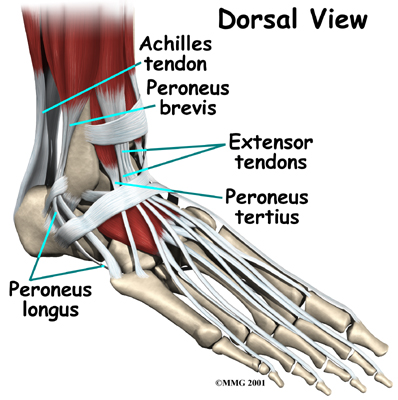

Ligaments on both sides of the ankle joint help hold the bones together. Many tendons cross the ankle to move the ankle and the toes. (Ligaments connect bones to bones while tendons connect muscles to bones.) The large Achilles tendon in the back is the most powerful tendon in the foot. It connects the calf muscles to the heel bone and gives the foot the power for walking, running, and jumping.